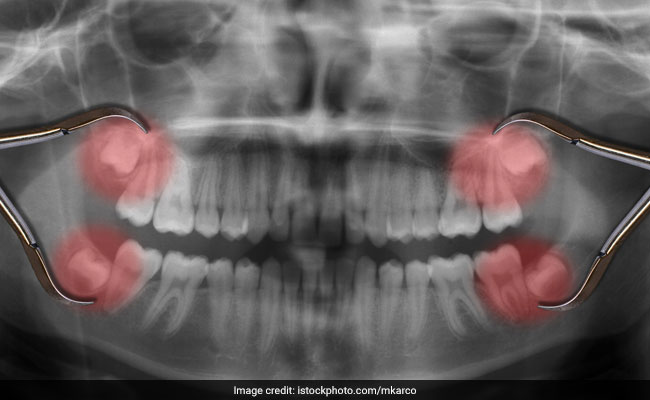

Around the ages of 17 to 21, we get around 4 wisdom teeth. The experience can be quite painful and unpleasant for some of us. Usually, emergence of wisdom teeth causes mild sensation of uneasiness. But because of insufficient space for these large third molars, wisdom teeth can cause anywhere between moderate to severe pain. Pains are severe when wisdom teeth get positioned in the wrong place and allow trapping of food particles. At times, the teeth emerge only partially and give room for bacteria to get into the gums and cause infection.